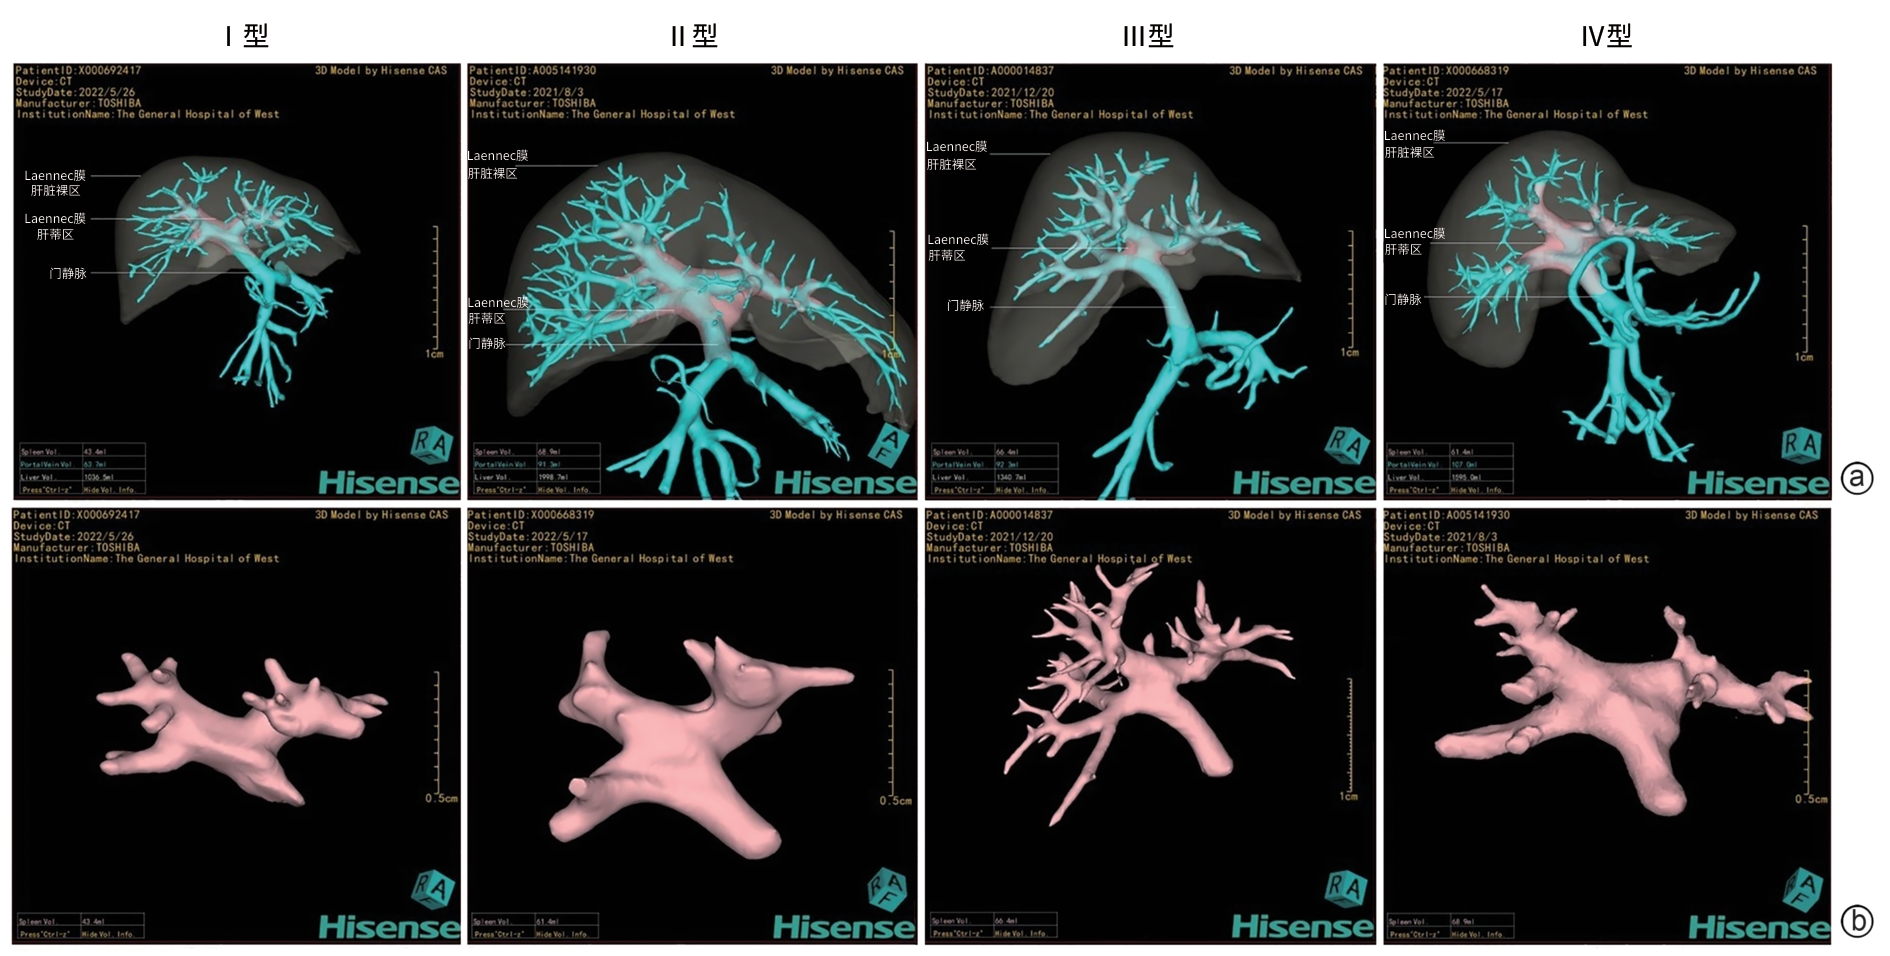

Liver Fibrosis and Liver Cirrhosis

Clinical and pathological features of patients with congenital hepatic fibrosis: An analysis of 26 cases

Shixuan LIU, Yujiao ZHANG, Ying ZHENG, Aiping SONG, Tailing WANG, Xiuhong WANG

2025, 41(11): 2317-2322. DOI: 10.12449/JCH251118

Abstract(102) HTML (25) PDF (2080KB)(43)

Abstract:

Objectives  To summarize the clinical and pathological features of patients with congenital liver fibrosis (CHF), and to investigate the differences in clinical and pathological features between patients in different age groups.  Methods  A retrospective analysis was performed for the clinicopathological data of 26 patients with pathologically confirmed CHF in China-Japan Friendship Hospital from August 2005 to June 2023, and the patients were stratified by age to investigate the clinical and pathological features of patients in different age groups.  Results  Among the 26 patients, there were 12 male patients and 14 female patients, with an age of onset of 4 — 61 years. There were 19 patients with portal hypertension type (73.08%), 2 patients with cholangitis type (7.69%), 4 patients with mixed type (15.38%), and 1 patient with occult type (3.85%). Of all 26 patients, 4 had unknown clinical symptoms, and among the 22 patients with clear clinical symptoms, 10 (45.45%) attended the hospital due to upper gastrointestinal bleeding caused by portal hypertension. Pathological manifestations included roughly normal liver parenchyma separated by fibrous septa in the portal area, with the presence of abnormal reactive bile duct hyperplasia. Denser fibrous septa and a lack of portal veins with the corresponding caliber were observed in 4 pediatric patients with disease onset before the age of 10 years, with a significant reduction or even disappearance of compensatory thin-walled blood vessels.  Conclusion  Portal hypertension-type CHF is the most common type in clinical practice. Patients with an early age of onset have certain histopathological features of the liver, with the presence of serious complications associated with portal hypertension. Therefore, liver biopsy should be performed for patients suspected of CHF in clinical practice, and genetic testing should be performed when necessary. Early identification and diagnosis are of great importance for improving the prognosis of patients.